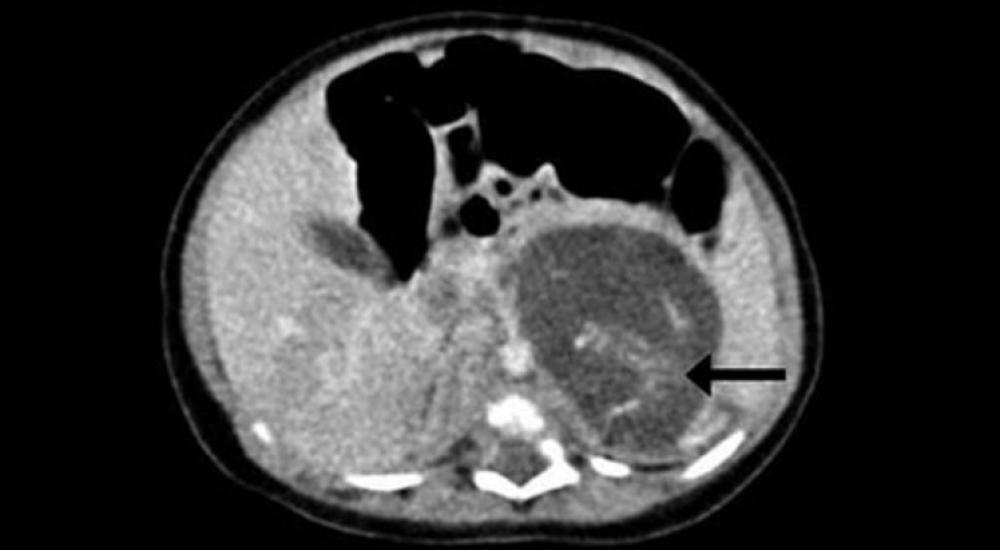

وأظهر تصوير جسم جنين المولودة بالموجات فوق الصوتية الذي أجري قبل ولادتها وجود انتفاخ غريب في منطقة بطنها.

وفي النتيجة أجرى الأطباء عملية لها بعد ثلاثة أسابيع من الولادة، ووجدوا جنينين بين كبدها وكليتها بوزن 9.3 غرام و14.2 غرام، ما يوافق فترتي الحمل لمدة سبعة وتسعة أسابيع.